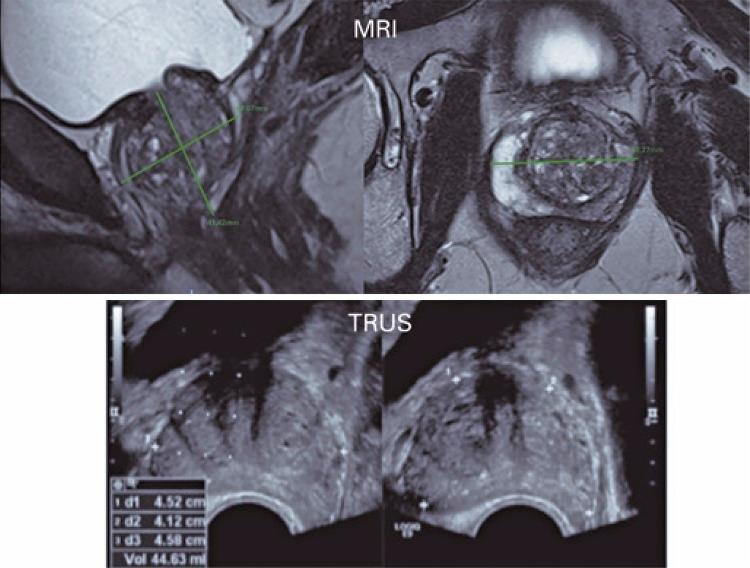

A retrospective study of 85 patients who underwent multiparametric magnetic resonance and transrectal ultrasound (for fusion image-guided biopsy) before radical prostatectomy. Prostate measurements were obtained from magnetic resonance axial and sagittal T2-weighted images and ultrasound; the prostate volume was determined using the ellipsoid formula. The results were compared with the surgical specimen weight. Maximum interval between multiparametric magnetic resonance imaging, transrectal ultrasound, and prostatectomy was 6 months.

The prostate volume measured by multiparametric magnetic resonance imaging was 18-157cm3 (mean of 49.9cm3) and by transrectal ultrasound, 22-165cm3 (mean of 54.9cm3); the surgical specimen weight was 20-154g (mean of 48.6g), with no statistical differences. Based on the values obtained from imaging examinations, the prostate volume obtained was very close to the real prostatic weight, and the measures by multiparametric magnetic resonance were slightly more precise.

Prostate volume measured by multiparametric magnetic resonance imaging and transrectal ultrasound showed similar values, and excellent agreement with real prostate weight of the surgical specimens. Prostate volume measured by magnetic resonance has been increasingly used in the clinical practice, and its value enables appropriate therapeutic planning and control of patients.